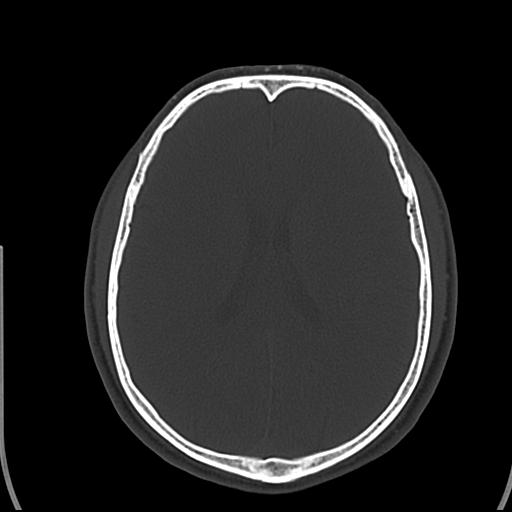

头皮下高密度结节影???临床上在老年男性比较常见。大家看看是什么?成因是? 本例患者,男性,51岁。外伤来诊。无染发史及发根植入史。

这种东西有时要结合触诊和望诊。